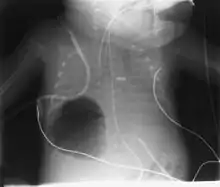

Los neumatoceles son especialmente frecuentes en niños y no deben confundirse con otras acumulaciones de gas en el tórax, como el neumotorax, las bullas que se producen en el enfisema pulmonar o el absceso de pulmón. Se diagnostican mediante una radiografía o TAC de tórax que permiten ver un espacio lleno de aire que contrasta con el parénquima pulmonar que lo rodea. Suelen desaparecer de manera espontánea, aunque en ocasiones es preciso realiza un drenaje mediante la inserción de un cateter para lograr su resolución.[1][2]